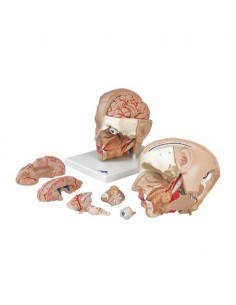

Scopri il Mondo dell’Anatomia con Modelli anatomici di Precisione

Modelli Anatomici Dettagliati per Ogni Necessità

Dal cranio in 22 parti con incastri magnetici ai modelli di colonna vertebrale, da quelli di articolazioni a quelli di cuore, ogni pezzo della nostra collezione è progettato per un’immersione totale nello studio dell’anatomia umana. I nostri modelli, realizzati tramite scansioni di ossa vere, garantiscono un’esperienza tattile autentica e una fedeltà di peso quasi identica agli originali.